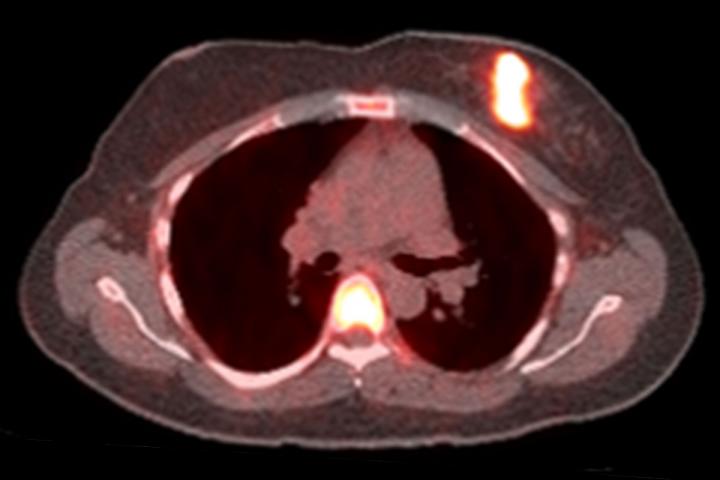

image: Bright spots indicate that cancer cells have responded to a one-day challenge with estrogen in this positron emission tomography (PET) scan of a woman with breast cancer. In a small study, researchers at Washington University School of Medicine in St. Louis found that only women whose tumors responded to estrogen challenge benefited from hormone therapy. The findings could help doctors choose the treatments most likely to help their patients.

Co-author John Katzenellenbogen, PhD, a chemist at the University of Illinois, designed an imaging agent to probe the number of progesterone receptors on the surface of cancer cells, in collaboration with the late Michael Welch, PhD, then a professor of radiology at Washington University. The compound, 21-[18F] fluorofuranylnorprogesterone (FFNP), attaches to progesterone receptors and can be detected with a positron emission tomogrophy (PET) scan. When more progesterone receptors are present, the PET signal is higher.

The women underwent a PET scan using FFNP, followed by three doses of estrogen over a 24-hour period, and then a second PET scan a day after the estrogen treatment.

For 28 women, the PET signal in the tumor increased considerably after exposure to estrogen, indicating that their estrogen receptors were working and had responded to the hormone by triggering an increase in progesterone receptor numbers. Fifteen women showed little to no change in progesterone receptor numbers after estrogen treatment.